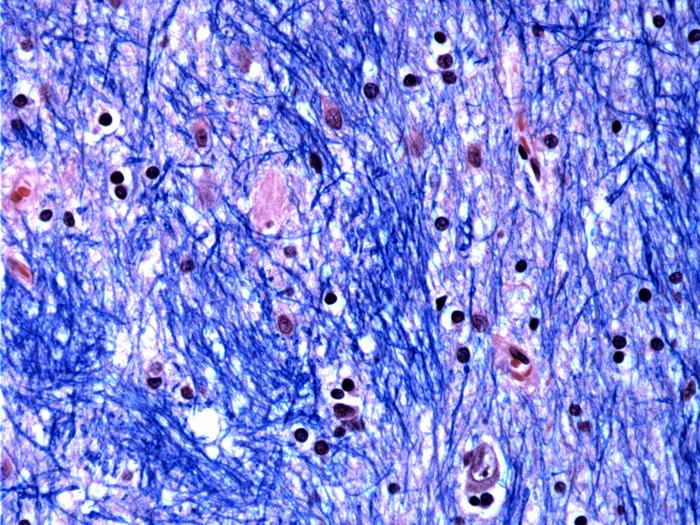

Huntington’s disease kills a population of cells called striatal projection neurons, which are located in the striatum, a structure deep in the brain responsible for movement, many cognitive functions, and motivation. When large numbers of these cells die, patients develop involuntary movements in the arms, legs, and face, and many patients also develop cognitive problems. These symptoms typically begin in mid-life and then progress over 10 to 20 years to more severe cognitive problems and difficulty moving or swallowing.

The researchers studied brain tissue donated by 53 people with Huntington’s and 50 without the disease, collected and preserved by the HBTRC. They analyzed more than 500,000 single cells and found that most cell types from people with the disease had essentially the same CAG repeat that they had inherited. But striatal projection neurons — the primary striatal cells that die in the disease — had greatly expanded their CAG-repeat tracts. Most previous research on human brain tissue had focused on CAG-repeat tracts of fewer than 100 repeats, but the new study showed that some neurons had as many as 800 CAGs, confirming a discovery made 20 years ago by Peggy Shelbourne at the University of Glasgow.